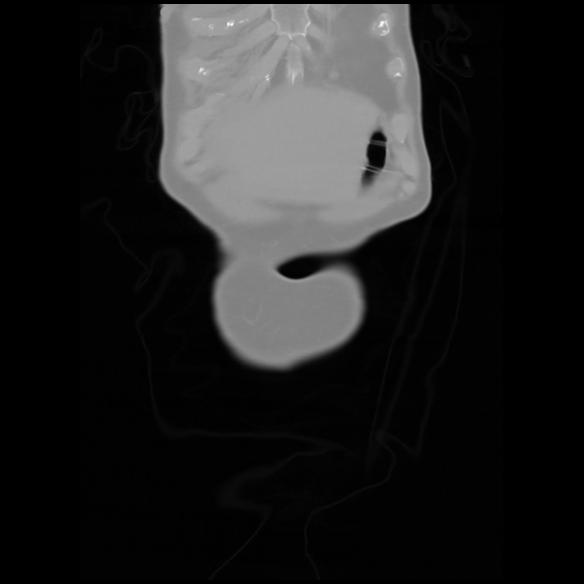

6 CUERPO,CE,Coronal,3.000,CUERPO,Coronal,